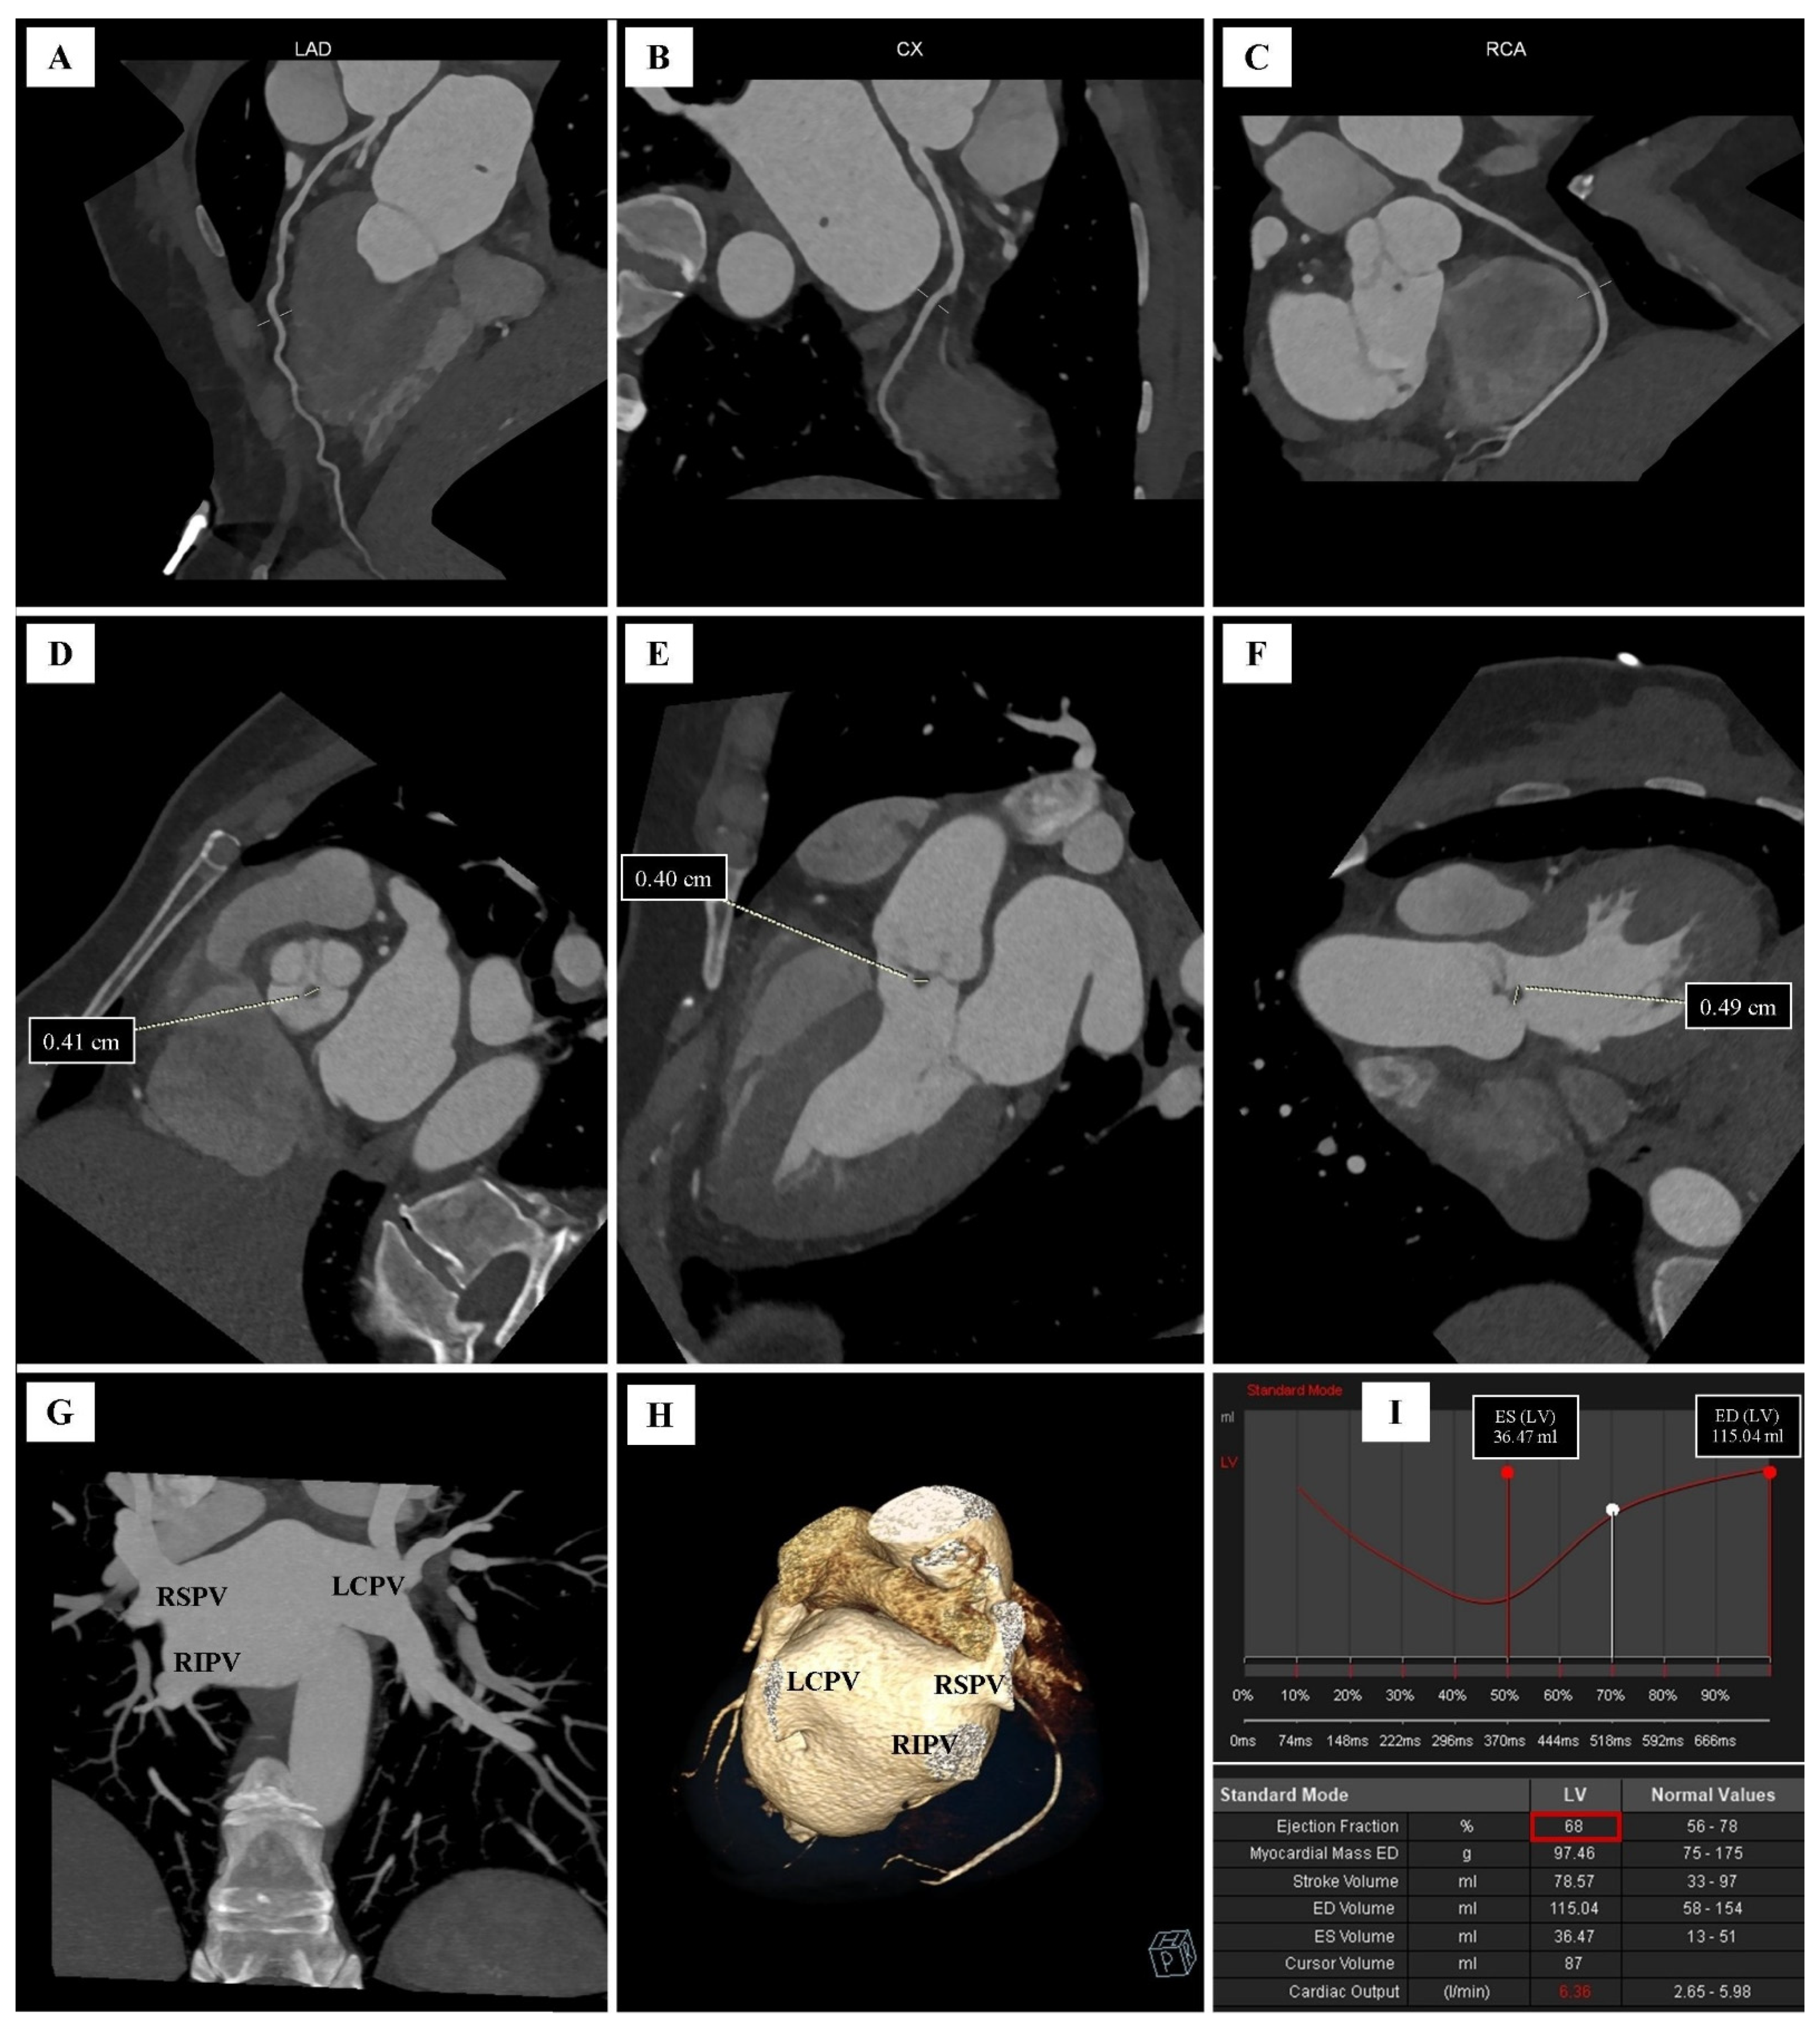

| Parameter | Value |

|---|---|

| Left ventricular mass (LVM) | 97.46 g |

| End-diastolic volume (EDV) | 115.04 mL |

| End-systolic volume (ESV) | 36.47 mL |

| Stroke volume (SV) | 78.57 mL |

| Ejection fraction (EF) | 68% |